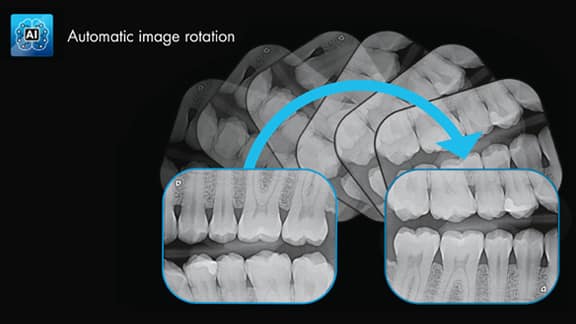

Détection de l’exposition des mauvais côtés

Rotation automatique de l’image

Reconnaissance automatique de la dent